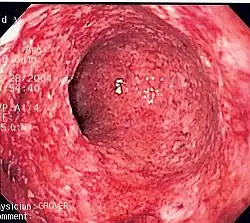

Colitis (inflammation of the colon) caused by Crohn's disease.

Inflammatory abnormalities are a large group of disorders that underlie a vast variety of human diseases. The immune system is often involved with inflammatory disorders, as demonstrated in both allergic reactions and some myopathies, with many immune system disorders resulting in abnormal inflammation. Non-immune diseases with causal origins in inflammatory processes include cancer, atherosclerosis, and ischemic heart disease.[9]